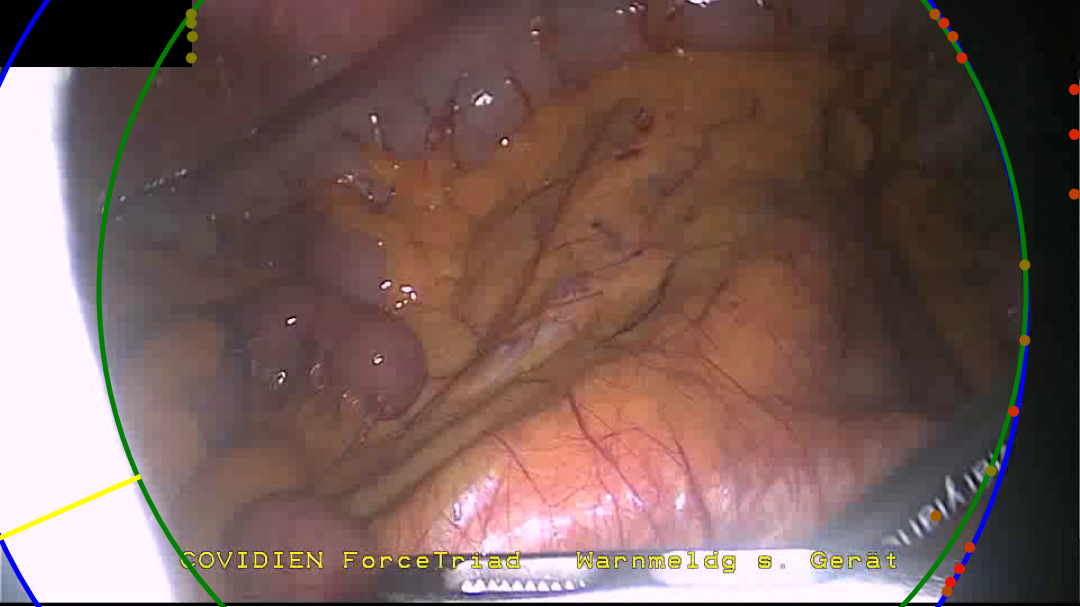

Delineation between the border and the content area of the image is made non-trivial by a few factors. Figure 3 shows a selection of endoscopic images demonstrating some of these difficulties. Firstly, while the border is generally a uniform black, a fair amount of low level noise is often observed, and imperfections in the scopes optics can result in aberrations such as bright spots, diffuse light bleeding outside of the content area, or imperfect circles. Secondly, the image within the content area may be adverse in that it can have low brightness or contain within it a secondary circular oculus, such as when the tip of the endoscope is only partially inserted through a trocar. Thirdly, while the circular image projection is generally centred around the middle of the image, it can in fact be significantly offset from the centre and its radius can fall within in a large range, even passing beyond the horizontal extent of the image for much of the image height. The spatial position and size of the circular image projection may also be surprisingly dynamic throughout an intervention, varying due to mechanical stresses placed through the endoscope and as the operator adjusts the zoom level on the camera. Finally, there can exist additional overlays such as secondary camera feeds, logos, and text.

Refer to caption

(a) A saturated area at the edge of the content area bleeds into the border.

(b) A dark content area leaves only a small segment of the circle visible.

(c) A partially cropped circle combined with a black overlay.

(d) Text overlays the content area and border.

(e) Structure within the top right quadrant of the content area appears as a misleading circle segment.

(f) A dark content area combined with a mostly cropped border provides a truly challenging example.

Figure 3: A selection of examples taken from our hand annotated dataset, chosen to portray some of the adverse features faced during endoscopic content area estimation.